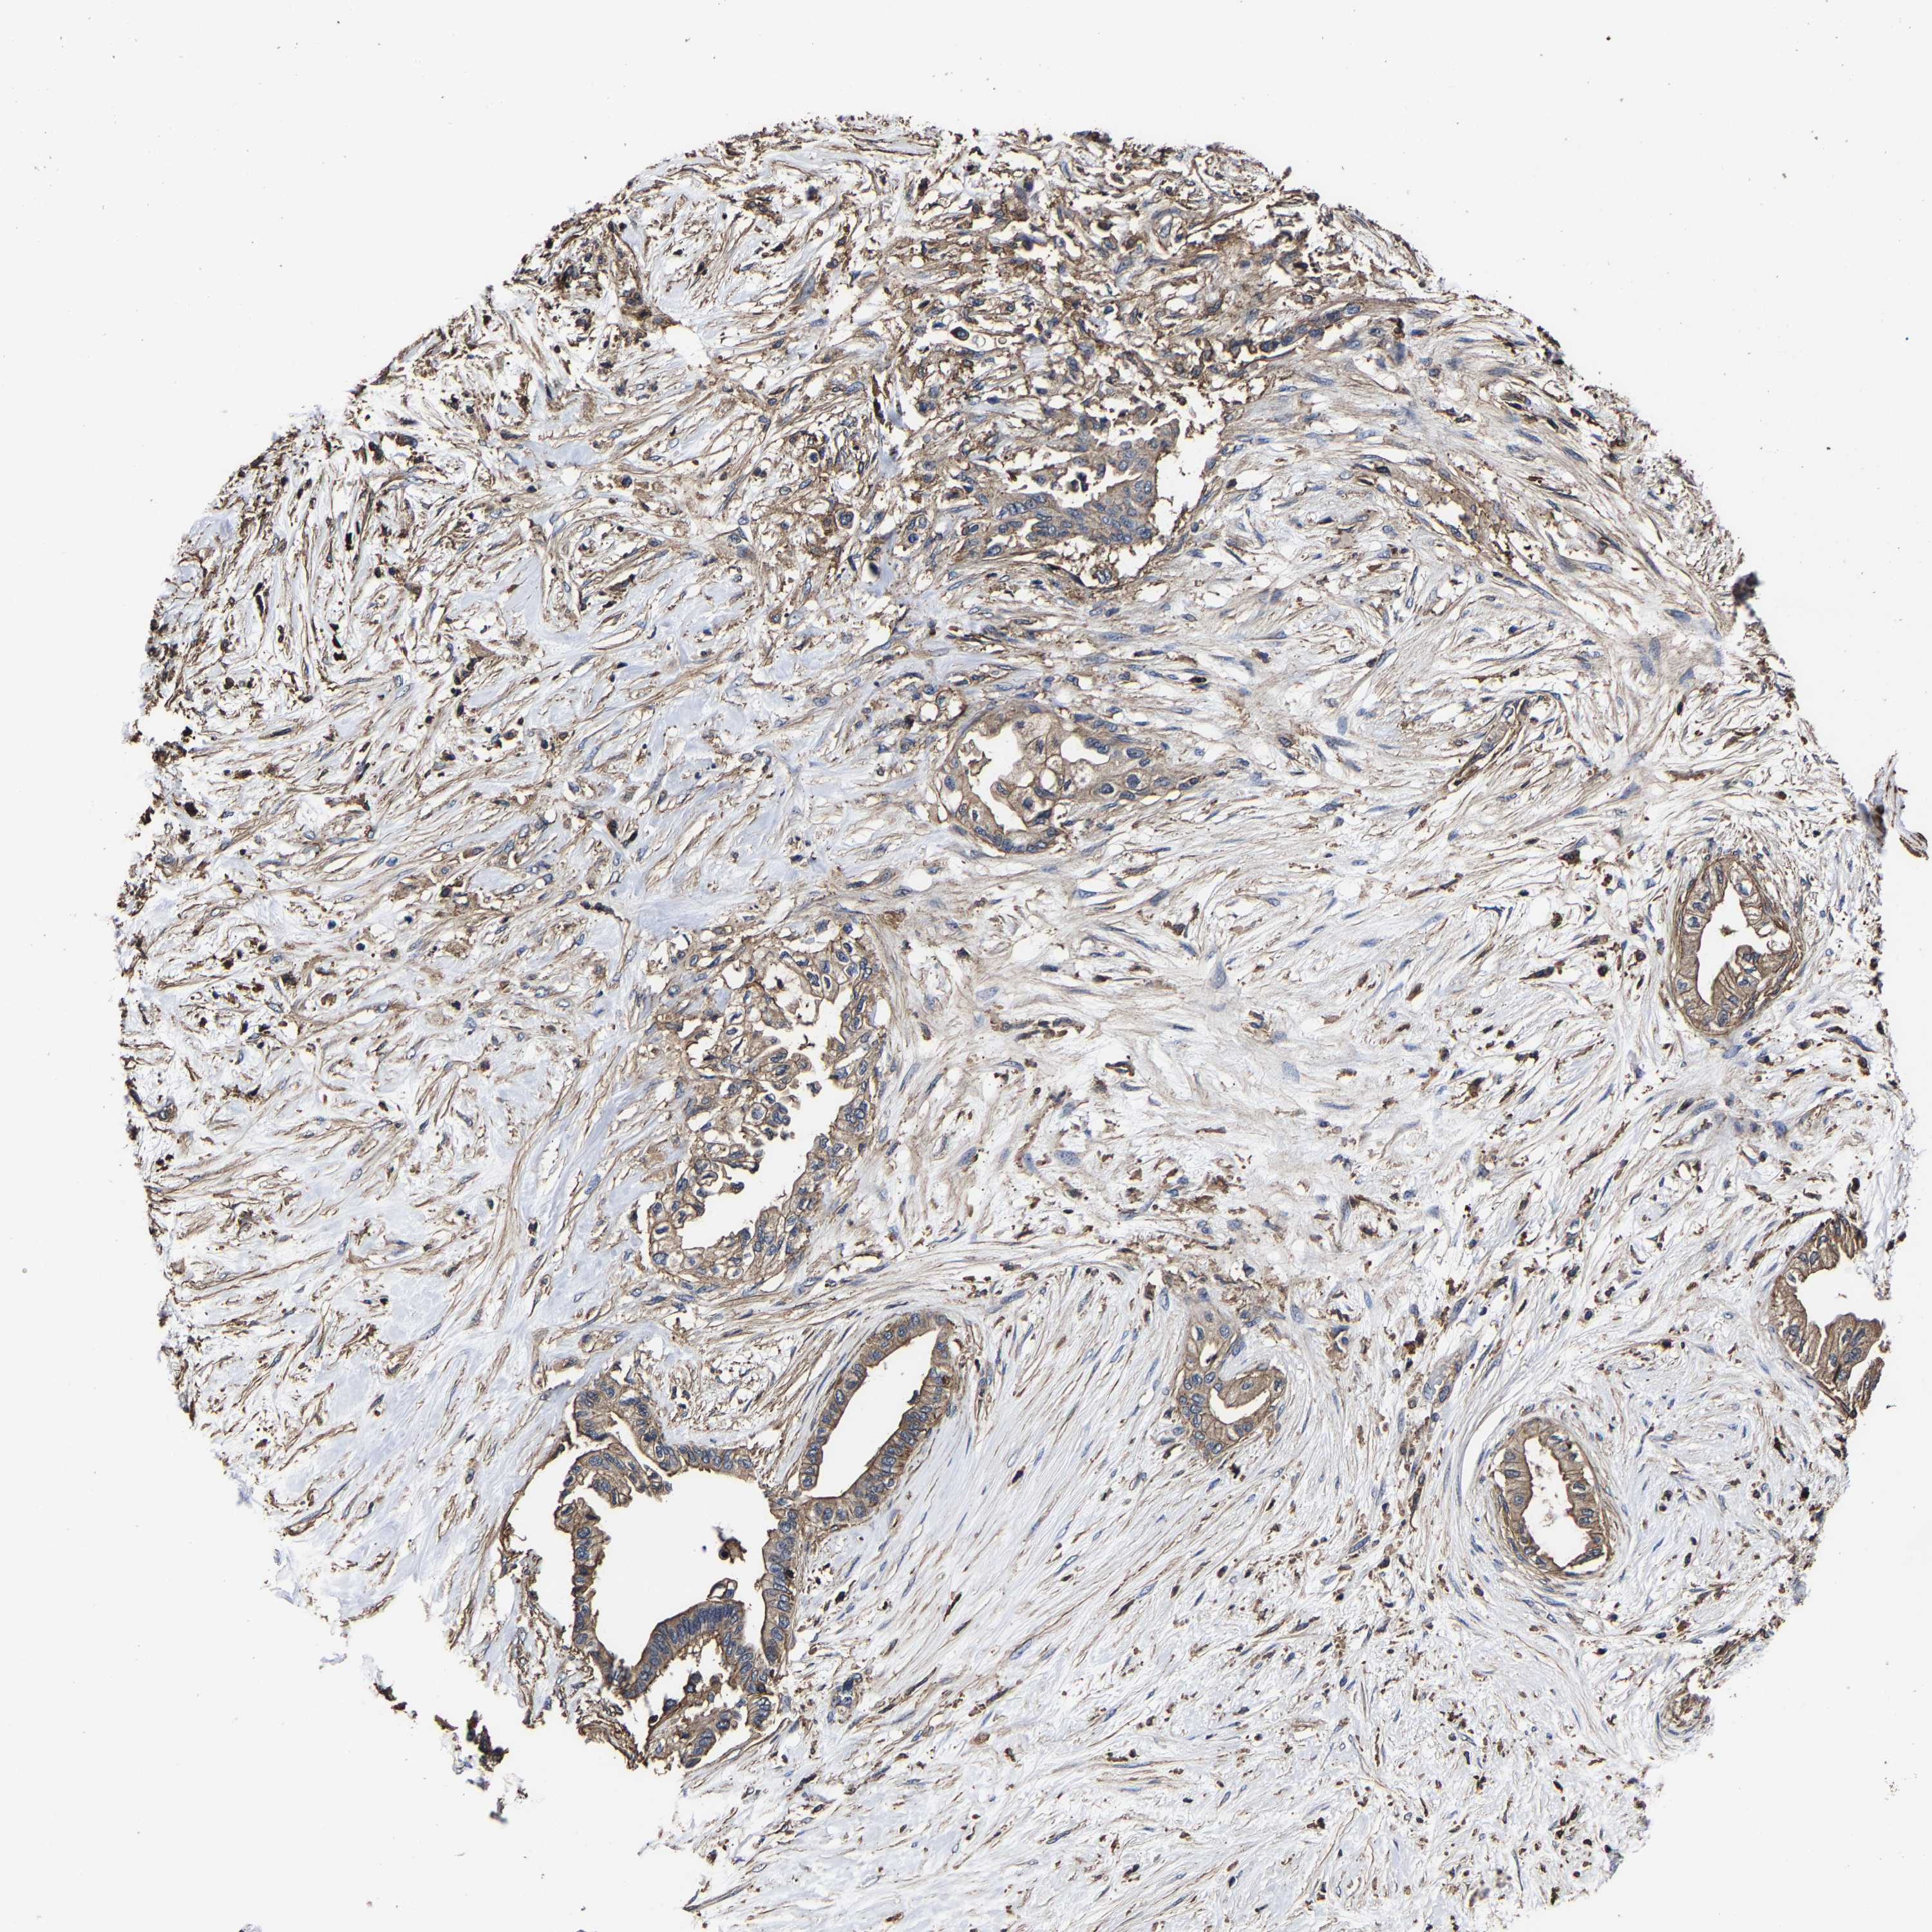

PANCREATIC CANCER - Protein expressioni

A mouse-over function shows sample information and annotation data. Click on an image to view it in a full screen mode. Samples can be filtered based on level of antibody staining by selecting one or several of the following categories: high, medium, low and not detected. The assay and annotation is described here.

Note that samples used for immunohistochemistry by the Human Protein Atlas do not correspond to samples in the TCGA dataset.

Antibody stainingi

Antibody staining in the annotated cell types in the current human tissue is reported as not detected, low, medium, or high, based on conventional immunohistochemistry profiling in selected tissues. This score is based on the combination of the staining intensity and fraction of stained cells.

Each image is clickable and will lead to virtual microscopy that enables deeper exploration of all samples and also displays staining intensity scores, fraction scores and subcellular localization as well as patient and tissue information for each sample.

Antibody HPA019949

Antibody HPA019957

Staining

High

Medium

Low

Not detected

Intensity

Strong

Moderate

Weak

Negative

Quantity

>75%

75%-25%

<25%

None

Location

Nuclear

Cytoplasmic/membranous

Cytoplasmic/membranous,nuclear

Adenocarcinoma, NOS